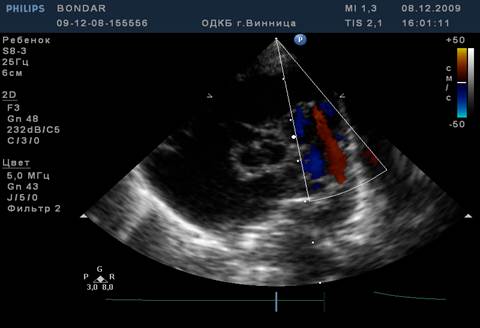

Об‘активно. Стан дитини середньої важкості. t 36,3 Шкіряні покриви бліді, „мармуровий” малюнок шкіри, періоральний та періорбітальний ціаноз. Задишка до 50 за хв.. Аускультативно – жорстке дихання, вологі та сухі хрипи. Пульс 146 за хв., ритмічний. Серцевий поштовх розлитий. Межі серця розширені вліво. Аускультативно – I тон на верхівці звучний,II акцентований та роздвоєний над легеневою артерією, систолодіастолічний шум в лівій підключичній ділянці. Печінка + 2 см. На ЕКГ – гіпертрофія лівого передсердя та шлуночка. На рентгенограмі – кардіомегалія за рахунок гіпертрофії лівого передсердя та шлуночка, підсилення легеневого малюнку, корені легень застійні.

На ЕхоКГ – поток крові з місця біфуркації легеневої артерії в протилежному (до датчика).